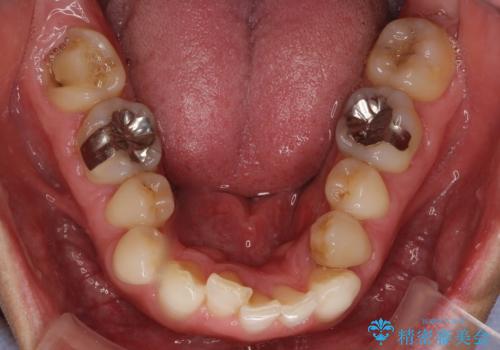

歯頚ラインが変えられないことや天然歯を削るリスクをご理解頂いた上で、オールセラミッククラウンによる補綴治療を行いました。(見えない奥歯のみ天然歯のままとしました)

下の前歯1本だけ歯軸を変えるために神経をとり根管治療を行っております。

それ以外の歯は神経をとらずに済むよう、慎重かつ丁寧に歯の形態を整えました。

治療前に埋伏している親知らずの抜歯をおすすめしましたが、ご希望されませんでした。